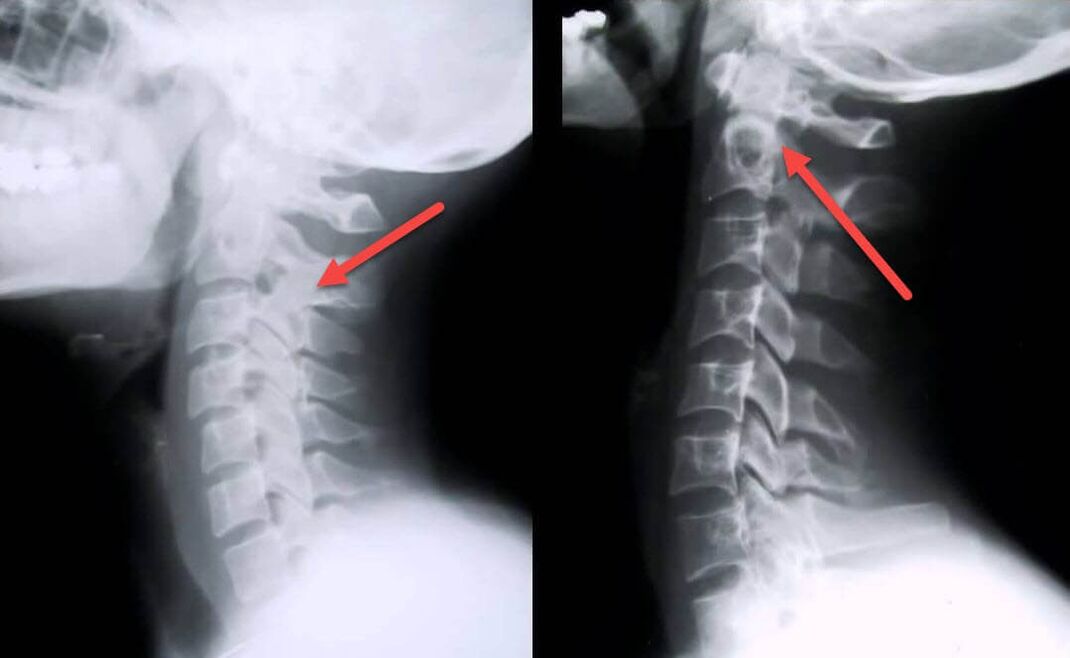

Kõige informatiivsem diagnostiline protseduur on radiograafia. 1. astme patoloogiad vastavad 1. või 2. radioloogilisele etapile. Saadud kujutised visualiseerivad haiguse tüüpilisi tunnuseid.

| I astme emakakaela osteokondroosi röntgeni etapid | Iseloomulikud märgid |

|---|---|

| 1. etapp | Väikesed muutused selgroo kõveruses emakakaela piirkonnas, mis mõjutavad ühte või mitut segmenti |

| 2. etapp | Lülisambavaheketaste kerge paksenemine, untsinate protsesside deformatsioon, lordoosi sirgendamine, luustruktuuride väikesed kasvud |